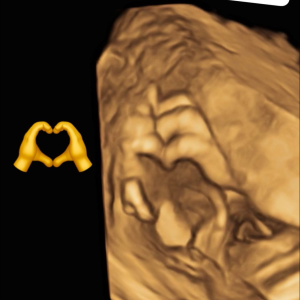

Diplômée en Echographie foetale et Gynécologique

Agrément National pour la réalisation des échographies du Premier Trimestre de grossesse